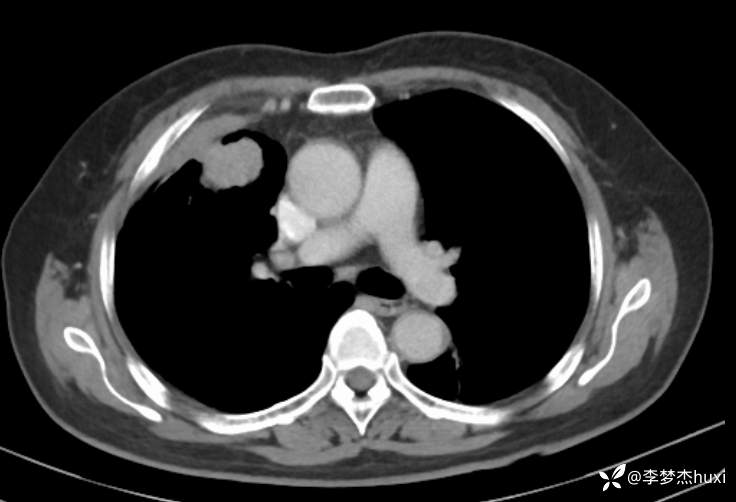

女性69岁,胸痛住院,检查发现肺占位性病变,猜病理

辅助检查:胸部CT:右肺占位?炎症?双肺炎性变,左肺下叶陈旧性病变,双肺纹理增多,主动脉及冠状动脉钙化,双侧胸膜局部增厚,胆囊结石,多发肝囊肿?请结合超声。

临床诊断:肺占位